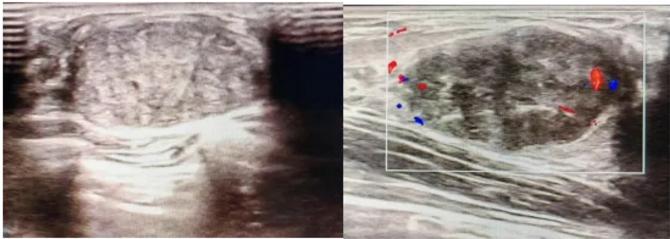

三、彩超檢查:無創(chuàng)檢查的“黃金眼”

高分辨率:可清晰顯示腫塊形態(tài)、血流信號,敏感度達80%-90%。

2.彩超報告關鍵指標

形態(tài):良性多呈橢圓形或分葉狀,邊界光滑。

縱橫比: 良性通常<1(橫徑>縱徑) 。

血流信號:纖維瘤血流較少,惡性常伴豐富雜亂血流。

鈣化:粗大鈣化多為良性,細小簇狀鈣化需警惕惡性。

BI-RADS分級:2-3類提示良性,4類以上需進一步檢查。

典型表現(xiàn):

橢圓形低回聲團塊,包膜完整,內部回聲均勻,后方回聲增強,周邊無“蟹足樣”浸潤。